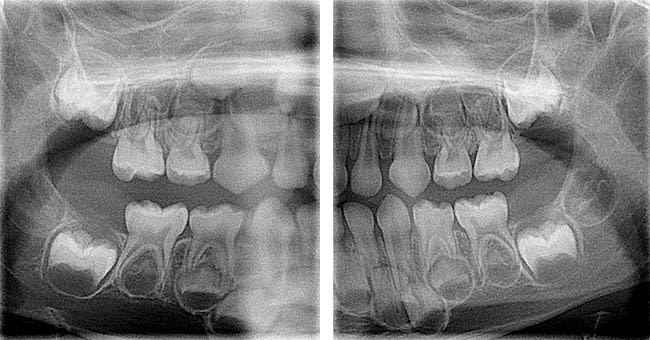

Several optional features are available on digital panoramic units from various manufacturers. Features include: 1) variable arch shapes; 2) curved linear projections of the temporomandibular joints, maxillary sinuses, and cross sections of the jaws; 3) automatic exposure control; and 4) panoramic bitewings (Figure 2).8-12

While a somewhat steep learning/training curve may be encountered when transitioning to digital intraoral imaging, the acquisition of digital panoramic images is essentially straightforward and very similar to analog film-based acquisition, assuming the staff has computer experience (Figure 3). Nevertheless, appropriate training should be included in any purchase agreement. Similarly, a warranty/service contract should be investigated to assure quick responses should the unit ever need maintenance or repair.